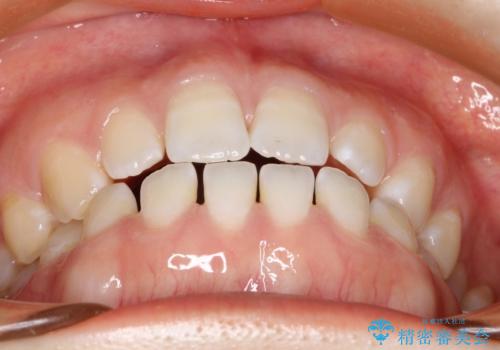

前歯の隙間を閉じたい インビザラインによる矯正

- 上下の前歯に隙間があるとのことで来院されました。

インビザラインにて隙間を閉じる矯正を行いました。

使用時間を守っていただけたので、比較的スムーズに矯正を終了することができました。